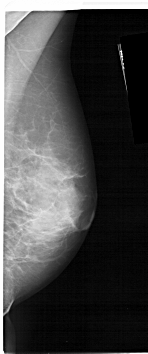

ics_version 1.0 filename A-1591-1 DATE_OF_STUDY 14 8 1990 PATIENT_AGE 52 FILM FILM_TYPE REGULAR DENSITY 4 DATE_DIGITIZED 7 1 1999 DIGITIZER HOWTEK 43.5 SEQUENCE LEFT_CC LINES 5131 PIXELS_PER_LINE 1531 BITS_PER_PIXEL 12 RESOLUTION 43.5 OVERLAY LEFT_MLO LINES 5386 PIXELS_PER_LINE 2011 BITS_PER_PIXEL 12 RESOLUTION 43.5 OVERLAY RIGHT_CC LINES 4651 PIXELS_PER_LINE 2011 BITS_PER_PIXEL 12 RESOLUTION 43.5 NON_OVERLAY RIGHT_MLO LINES 5296 PIXELS_PER_LINE 2206 BITS_PER_PIXEL 12 RESOLUTION 43.5 NON_OVERLAY |